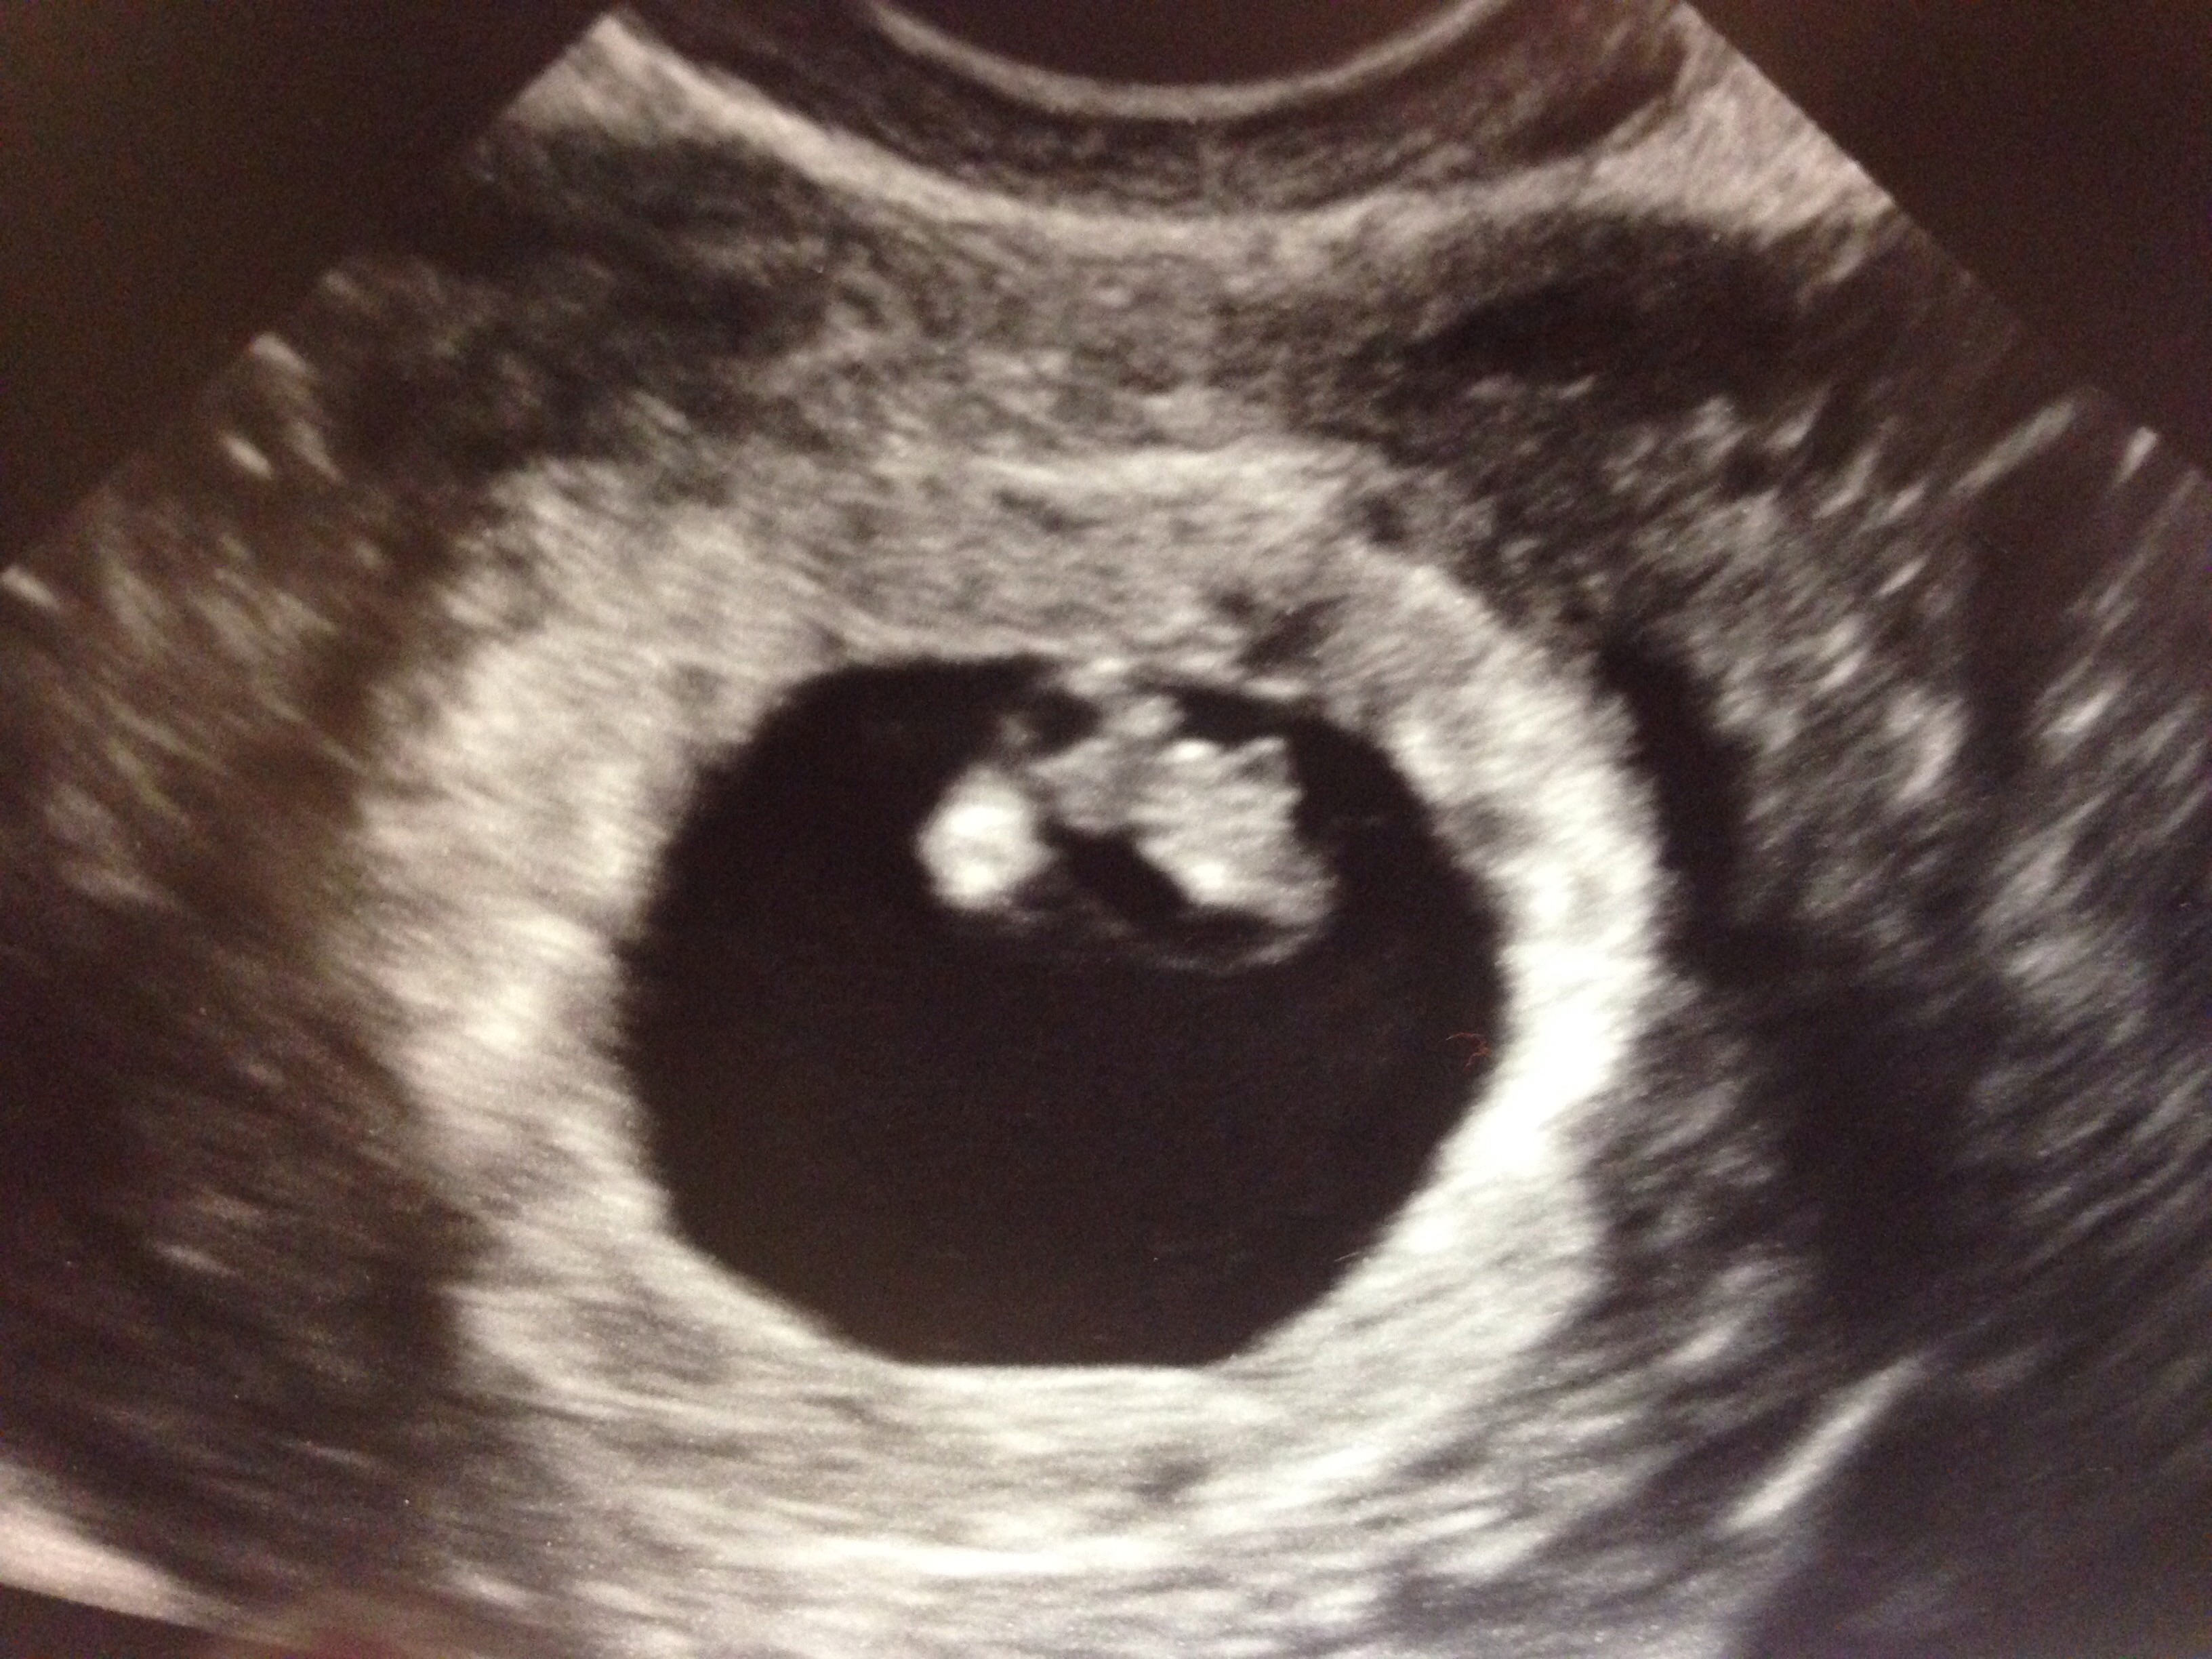

This was last Tuesday. Baby measured 6 w 3 days and had a strong heart rate of 128. I have another tomorrow. The only reason I'm getting all these ultrasounds is because I am a fertility patient. Although I conceived naturally this time, I am still being monitored by my RE because of a history of MC.